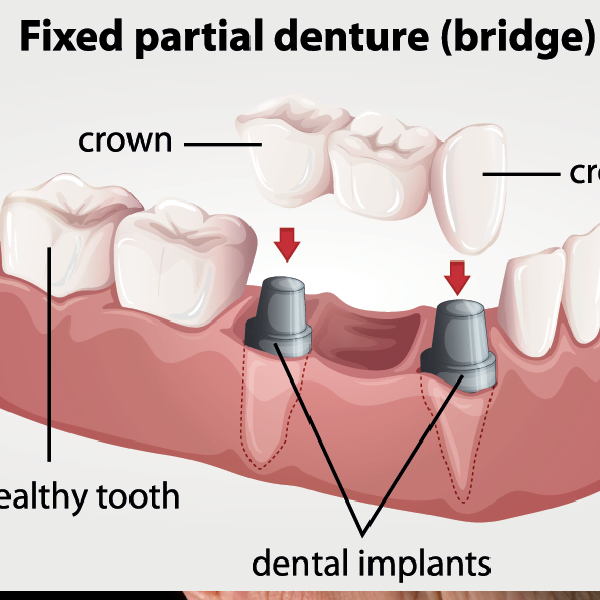

The Dental Implant Procedure

The dental implant process is a carefully scheduled and carried out procedure at Dr. Prakash Gupta's Dental Clinic. Below is a quick summary